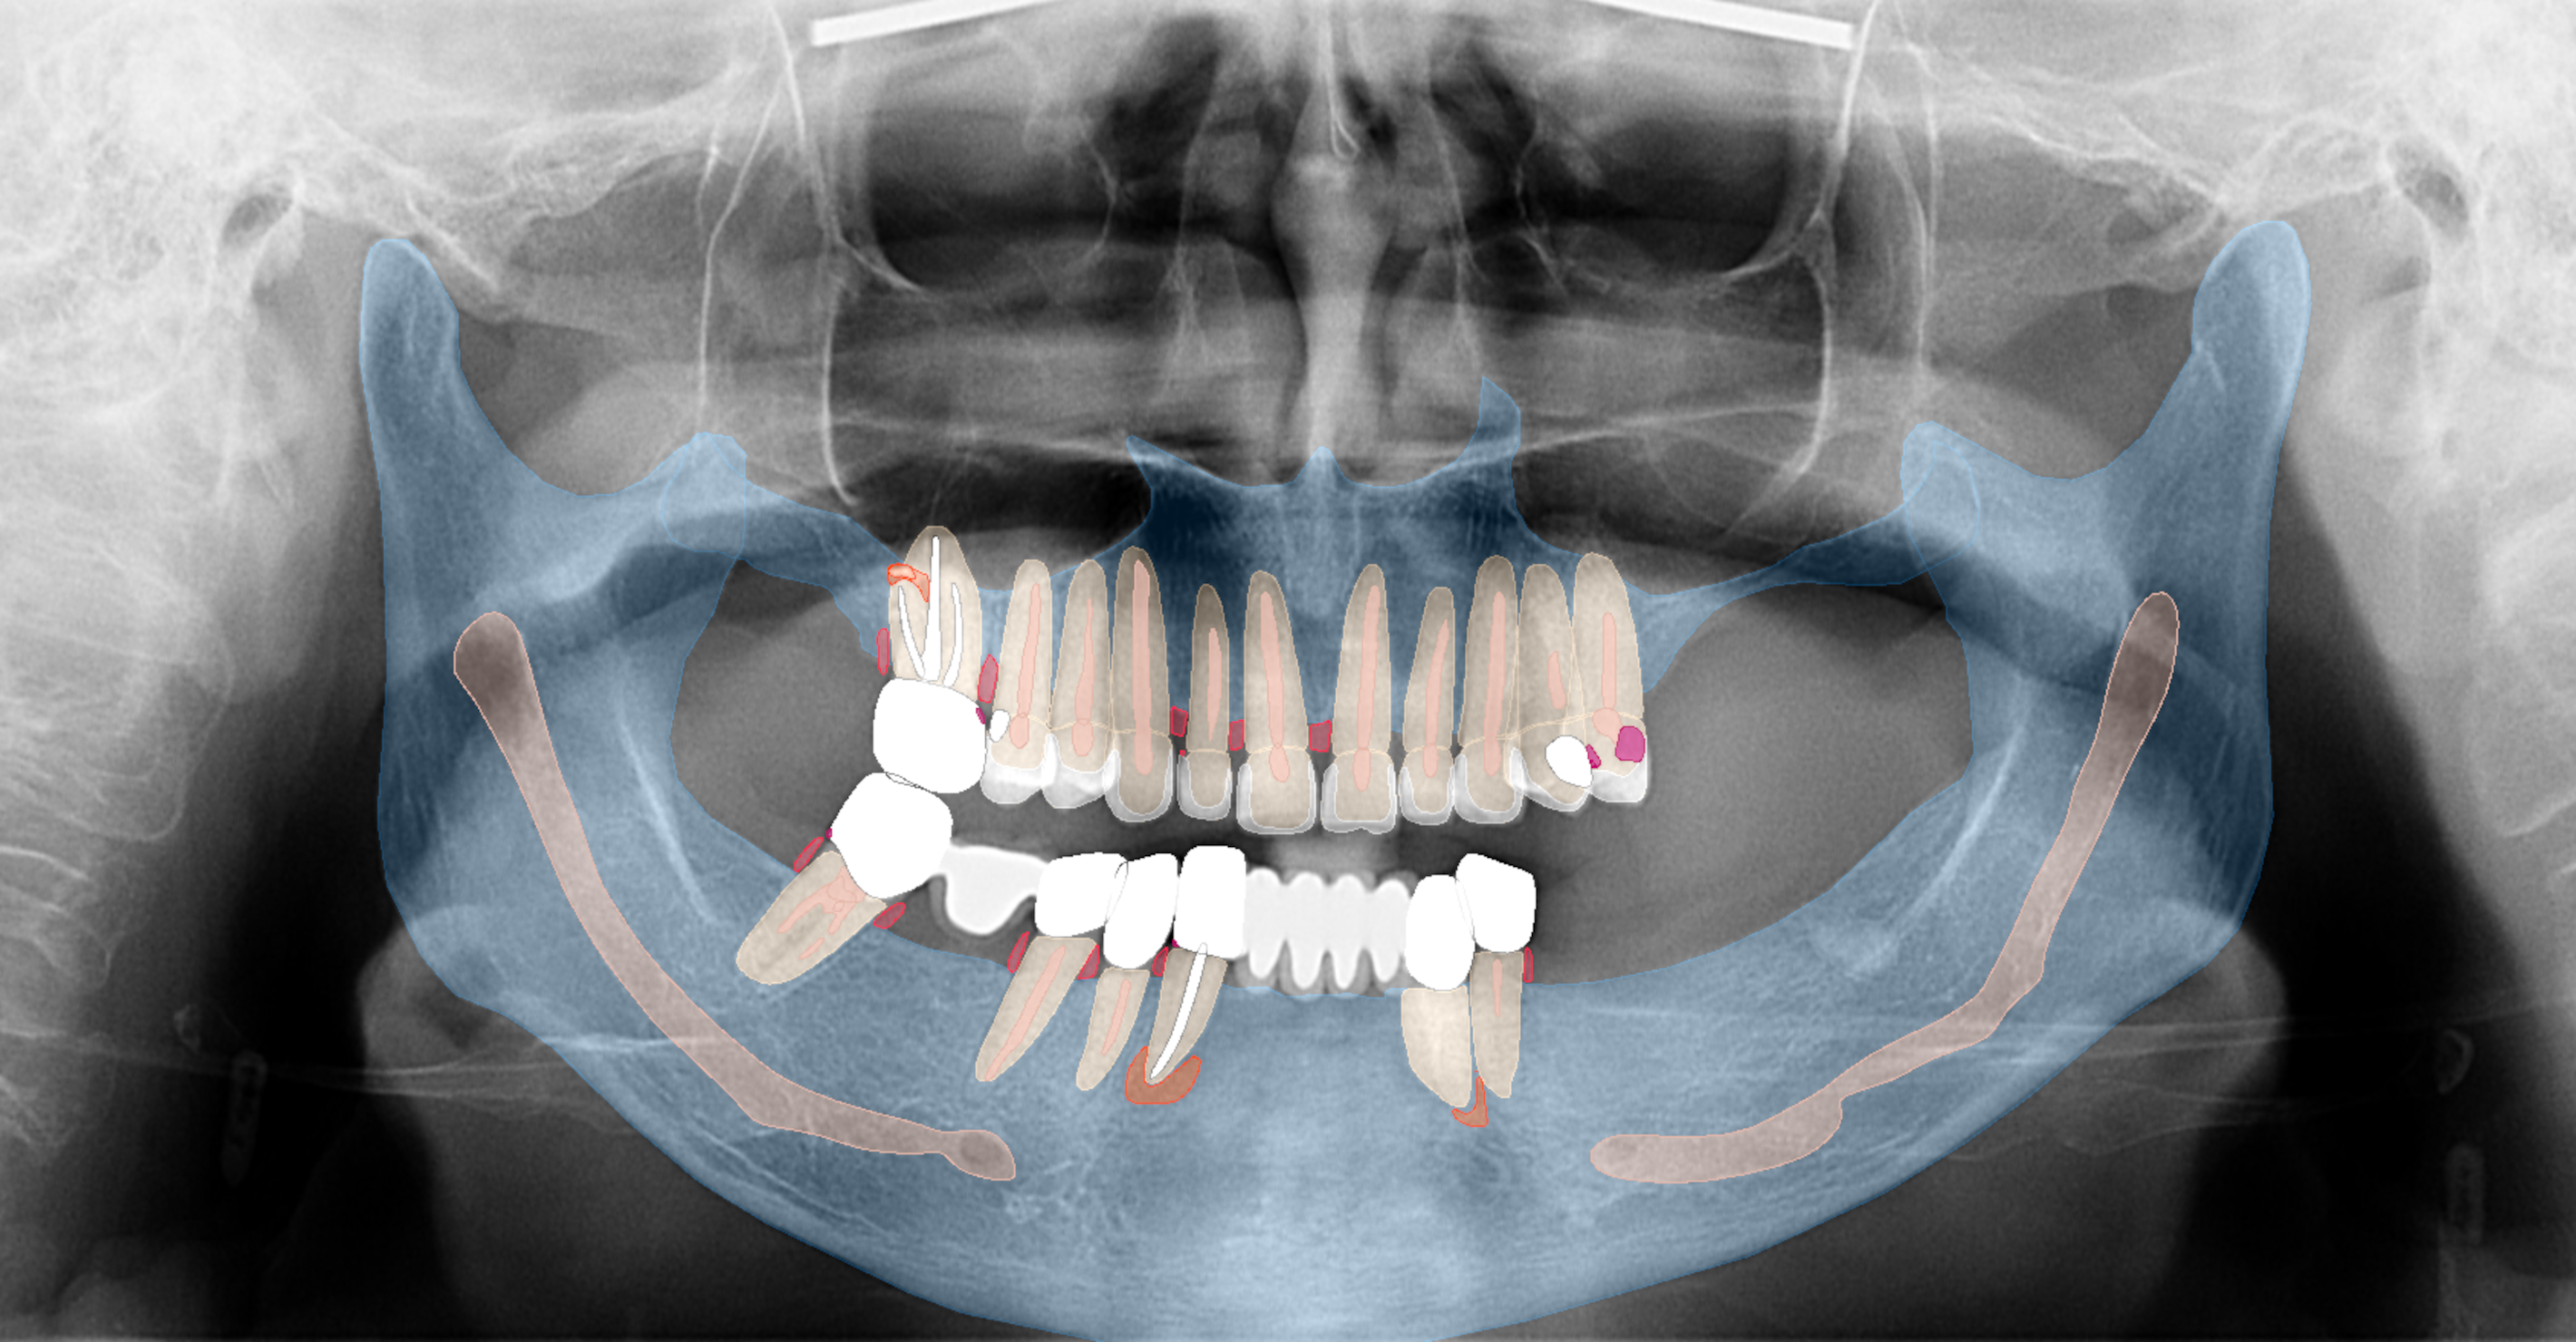

Intra-oral examination revealed compromised mandibular dentition, an old fixed prothesis, missing posterior teeth on the left side, periodontal involvement and gingival inflammation. A panoramic radiograph was obtained, and the findings were reported to the patient (Figs. 1a & b; 2a & b). Both mandibular canines had visible periapical radiolucencies. A CBCT scan was performed for a more detailed assessment of the alveolar bone anatomy (Figs. 3a & b). Temporomandibular joint examination revealed no indication of dysfunction (crepitus, clicking or pain).

Figs. 3a & b: Segmented CBCT scan (a). Mandibular arch morphology after virtual teeth extractions (b).

Fig. 3b